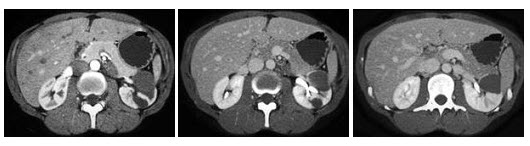

7、单项选择题

男,53岁,体重明显下降而行CT检查,如图所示,下列说法正确的是()

A.右肾区可见不规则的软组织块,增强为不均匀强化

B.肾平面以上的下腔静脉内均有软组织密度影

C.右心房内可见充盈缺损

D.此为右侧肾癌

E.癌栓侵入下腔静脉并扩散至右心房